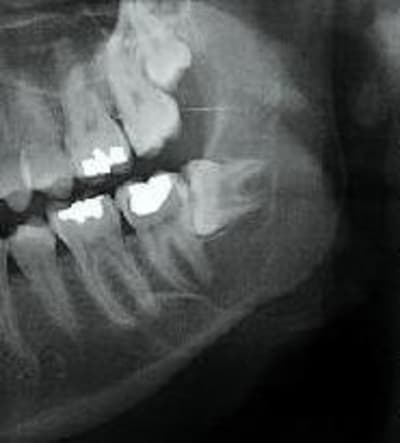

Ensuite scan

j'ai le scan mais pas ici la corticale linguale est reduite à sa plus simple expression et le kyste remonte sur le trajet du nerf et s'etend aussi en vestibulaire

A priori vu l'évolution sur les radios et l'âge de la patiente je pense qu'il s'agit d'un kératokyste en première intention.

éventullement un améloblastome.

ça peut être également un kyste dentigère laissé en place car il me semble que le kyste est déjà présent sur la première pano et elle est en rapport partiel avec le collet de 38 enclavée mais ça n'est pas caractéristique.